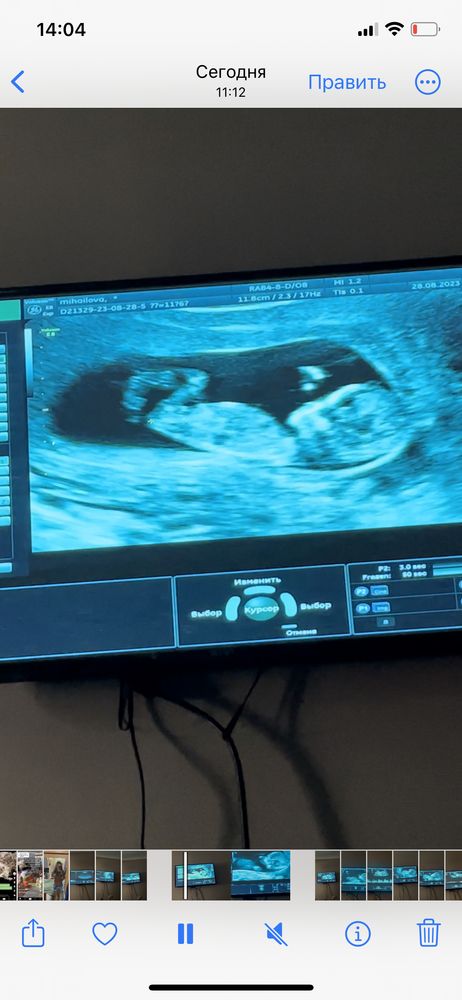

Кто расшифрует показатели по скринингу и пол малыша?🙈 Была сегодня на скрининге 🥹 срок по узи и месячным день в день. Пол сказала узистка даже смотреть не будет, как я не просила, сказала она мне терпеть 🥲 отправлю замерчики😁 правда они на укр языке. Посмотрите знающим глазом 😁🫂 и может кто по фото поймёт пол малыша, интерес берет своё

Настенька, ну по этому узи у вас девочка) Так как если фото узи перевернуть, то эмбрион будет слева, а слева по тесту Рамзи закреплены девочки, у меня совпало. Единственное у меня полукруг был вверху, а у вас на фото внизу, не знаю, зависит ли от него расположение эмбриона или нет.

Генриетта , а вот здесь можно посмотреть по половому бугорку, тут у вас тоже похоже на девочку.